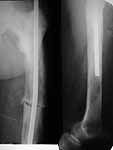

A male 76 years old sustained femoral shaft fracture after minimal

injury. Open reduction and intramedullary nailing was performed

somewhere else. He was refferred to us with pain in the femur and sense

of movement at the site, especially with rotation. Xrays revealed except

nonunion some bone structue changes. What is this? Isn't it Paget's

disease?

I believe its Pagets. The bone looks larger than normal, along with coxa vara, which is characteristic. Check his alkaline phophatase. In rare instances, you can see aggressive lytic disease (unlikely here), which requires medical Rx to quiet down. Get out your reamers, and put a big nail in him- the biggest his canal will take. Make it longer, and lock if you don't believe the fixation is snug.

From the appearance of the x-rays and the description of a fracture after minimal trauma, I would be very concerned about a neoplastic process. Odds would favor something metastatic and appearance might suggest a combined blastic-lytic lesion. I am particularly concerned about the lytic appearance distal to the end of the rod. I would work up the patient for both neoplastic and metabolic process before proceeding. After diagnosis treatment options can be considered. Dying to know what this is.

The femur is Pagetic.

It looks like Paget's disease to me. The original nail is small, short and unlocked. Make the second one reamed, large (14 mm), long (past the distal lucency) and statically locked for rotational control. Send tissue for pathology.